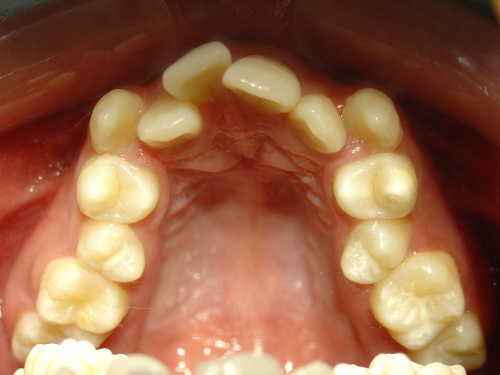

相信每個人都不希望自己擁有一口錯亂不齊的牙齒,這樣的牙齒不僅會成為別人取笑的例子,還常會影響我們的口腔健康,長期下去容易產生各種口腔疾病。許多人想要改變卻不得其法,那么怎么樣治療牙列不齊

順德德倫口腔醫院專家表示:治療牙列不齊比較常見的方式就是進行矯治,通過矯正可以很好的讓歪斜的牙齒排列整齊,重新找回自信。但是做矯治一定要做好“長期戰斗”的心理準備,牙齒矯正是通過牙套的方式讓歪斜的牙齒一點一點的回到正確的位置上,一般需要1-3年。帶完牙套后遠遠沒有結束,還需要帶半年至一年的保持器。

怎么樣治療牙列不齊?治療牙列不齊選擇哪種矯治方法好呢?順德德倫口腔引進的隱適美隱形矯正可以更好的解決您的問題。隱適美隱形矯正是一種三維診斷,個性化設計與數字化成形的無托槽隱形正畸技術。 可以通過電腦設計矯治器,讓臨床操作更加簡單。而對患者來說,隱形矯治器更加舒適、美觀、減少了患者的矯治痛苦。